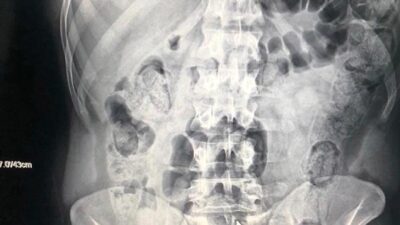

Yolcu kılığına girdiler! Hepsi midelerinden çıktı